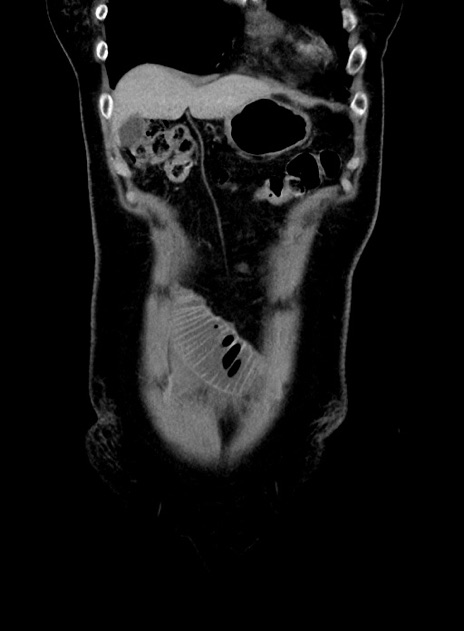

症例9(冠状断像)

【症例】 60歳代女性

【主訴】むかつき、みぞおちの痛み

【現病歴】3日前よりむかつきがあり、食事がとれない。

【既往歴】糖尿病

【身体所見】発熱なし、心窩部圧痛軽度あるも、腹膜刺激症状なし。

【データ】WBC 7400、CRP 1.92